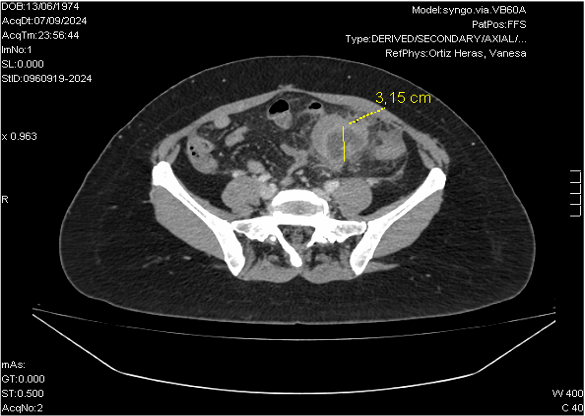

Ante la sospecha de EIP, TAC abdominal, confirma colección multiloculada en hemipelvis izquierda, en probable localización parametrial, sugestiva de absceso tubo-ovárico. Cambios inflamatorios locorregionales con leve engrosamiento de un segmento corto de sigma adyacente probablemente por contigüidad. Lesión focal hepática inespecífica, que en el contexto no permite descartar absceso secundario a embolismo séptico.

Juicio clínico: Enfermedad inflamatoria pélvica con absceso tuvovárico izquierdo.